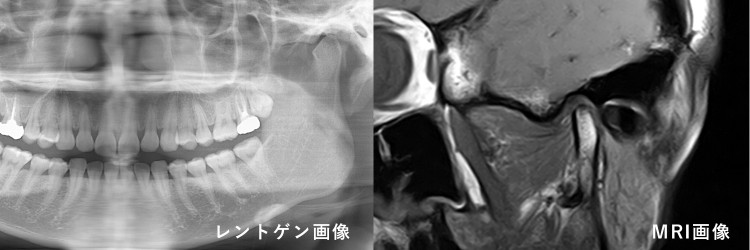

このように顎関節は骨だけでなくクッションとなる関節円板、関節円板と骨に繋がる多くの筋など軟組織で構成されています。そのためにレントゲンや歯科用 CT だけでは情報が圧倒的に不足します。そのため肘や膝の関節を治療する整形外科と同様に MRI での検査が必須になります。